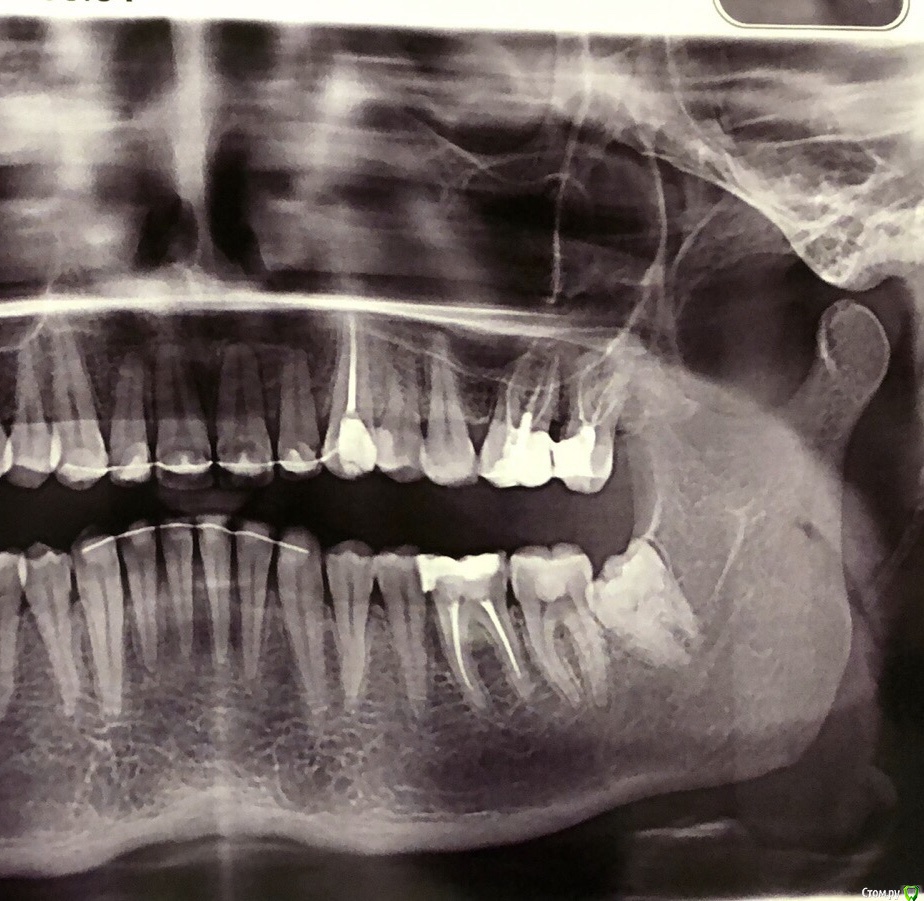

Здравствуйте, месяц назад пролечила верхние 6,7 по поводу пульпита. Неделю после лечения болела 6. Затихла на неделю и вот уже 3 неделю болит по ночам, иногда днём после еды. Врач говорит костный карман. Легче не стало, назначила антибиотик. Пью 3 дня, зуб 1 ночь не болел, на 2 ночь опять резко заныл. Не могу понять - менять врача или?

Врач говорит если аб не поможет то будет полностью перелечивать. Сегодня назначила электрофорез

На снимке есть нависание пломбы- уже убрала врач

По: показывала снимок другому врачу- сказал проблесков каналы хорошо, но из-за костного кармана нужна коронка